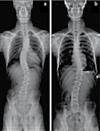

40 콜로라도 타임즈 · 2023년 4월 20일 목요일 · 1073호 [연예기사] 교통사고 후유증 / 목 통증 / 목 디스크 / 오십견 / 어깨통증 말초신경장애: 손, 발, 다리의 통증, 저림, 근육약화감, 감각상실 (편)두통 / 불면증 / 어지러움 / 턱관절 장애(TMJ) 척추측만증(Scoliosis) / 척추협착증 / 허리수술 후유증 허리통증 / 허리 디스크 / 관절염 / 좌골신경통 / 고관절, 발목, 손목 통증 ▪ ▪ ▪ ▪ ▪ ▪ ▪ ▪ ▪ 최첨단 목/허리 디스트 치료기기 최신형 디지털 X-ray 시설 Therapeutic Massage ▪초음파, 전기치료 Gonstead Chiropractic 교정치료 치료 진료과목 교통사고 치료 전문 자동차 보험 건강 보험 상해 보험 Southern California University of Health Science Doctor of Chiropractic 콜로라도주 척추신경 보드 정회원 캘리포니아주 척추신경과 보드 정회원 National Board 척추신경과 정회원 손석기 D.C. 원장, 척추신경 전문의 chiro1health@gmail.com Open Hours 월/수/금 9am-6pm 화/목: 2pm-6pm 청소년을 위한 척추교정 프로그램